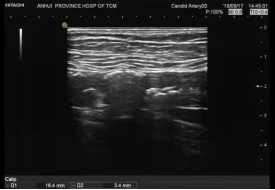

用药效果:丹蛭降糖胶囊对2型糖尿病合并下肢大血管病变治疗前后下肢多普勒超声比较

治疗后

基础降糖治疗患者治疗后下肢多普勒超声图无明显改善,基础治疗的基础上加用丹蛭降糖胶囊口服患者治疗后下肢多普勒超声图显示下肢动脉内-中膜厚度稍下降,斑块面积稍有缩小。